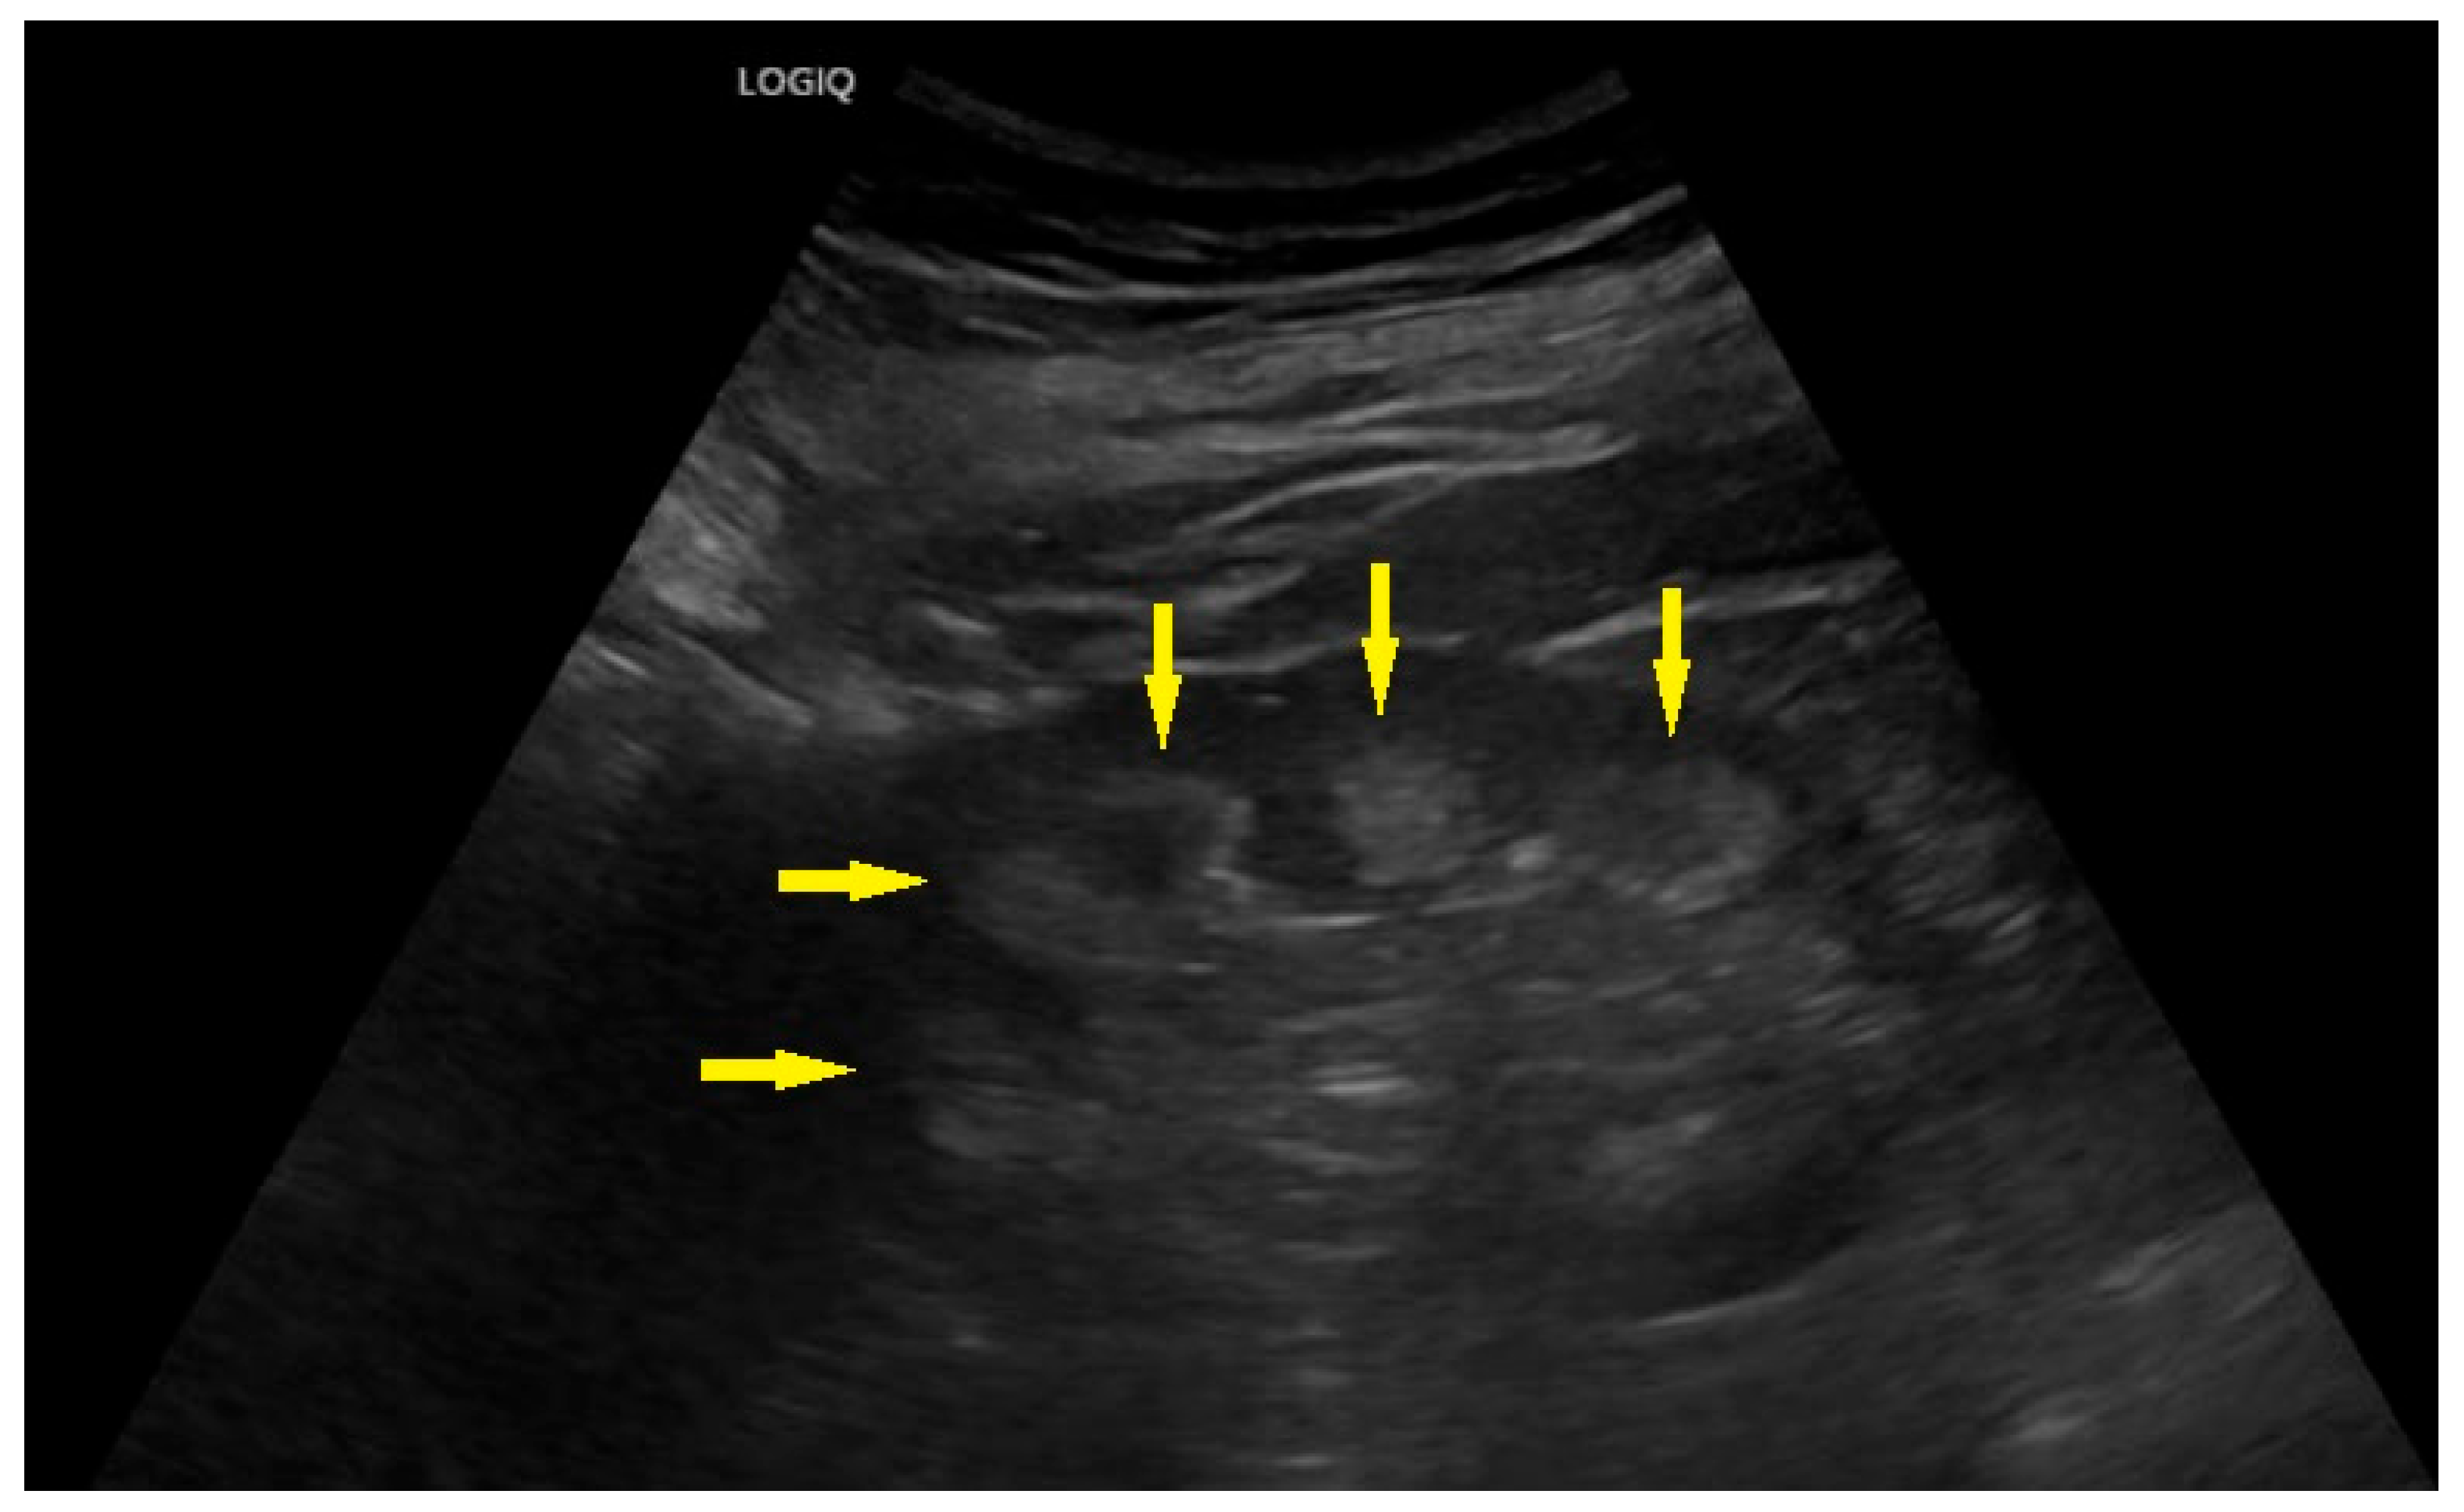

| Nephrocalcinosis | yes | no | no | |